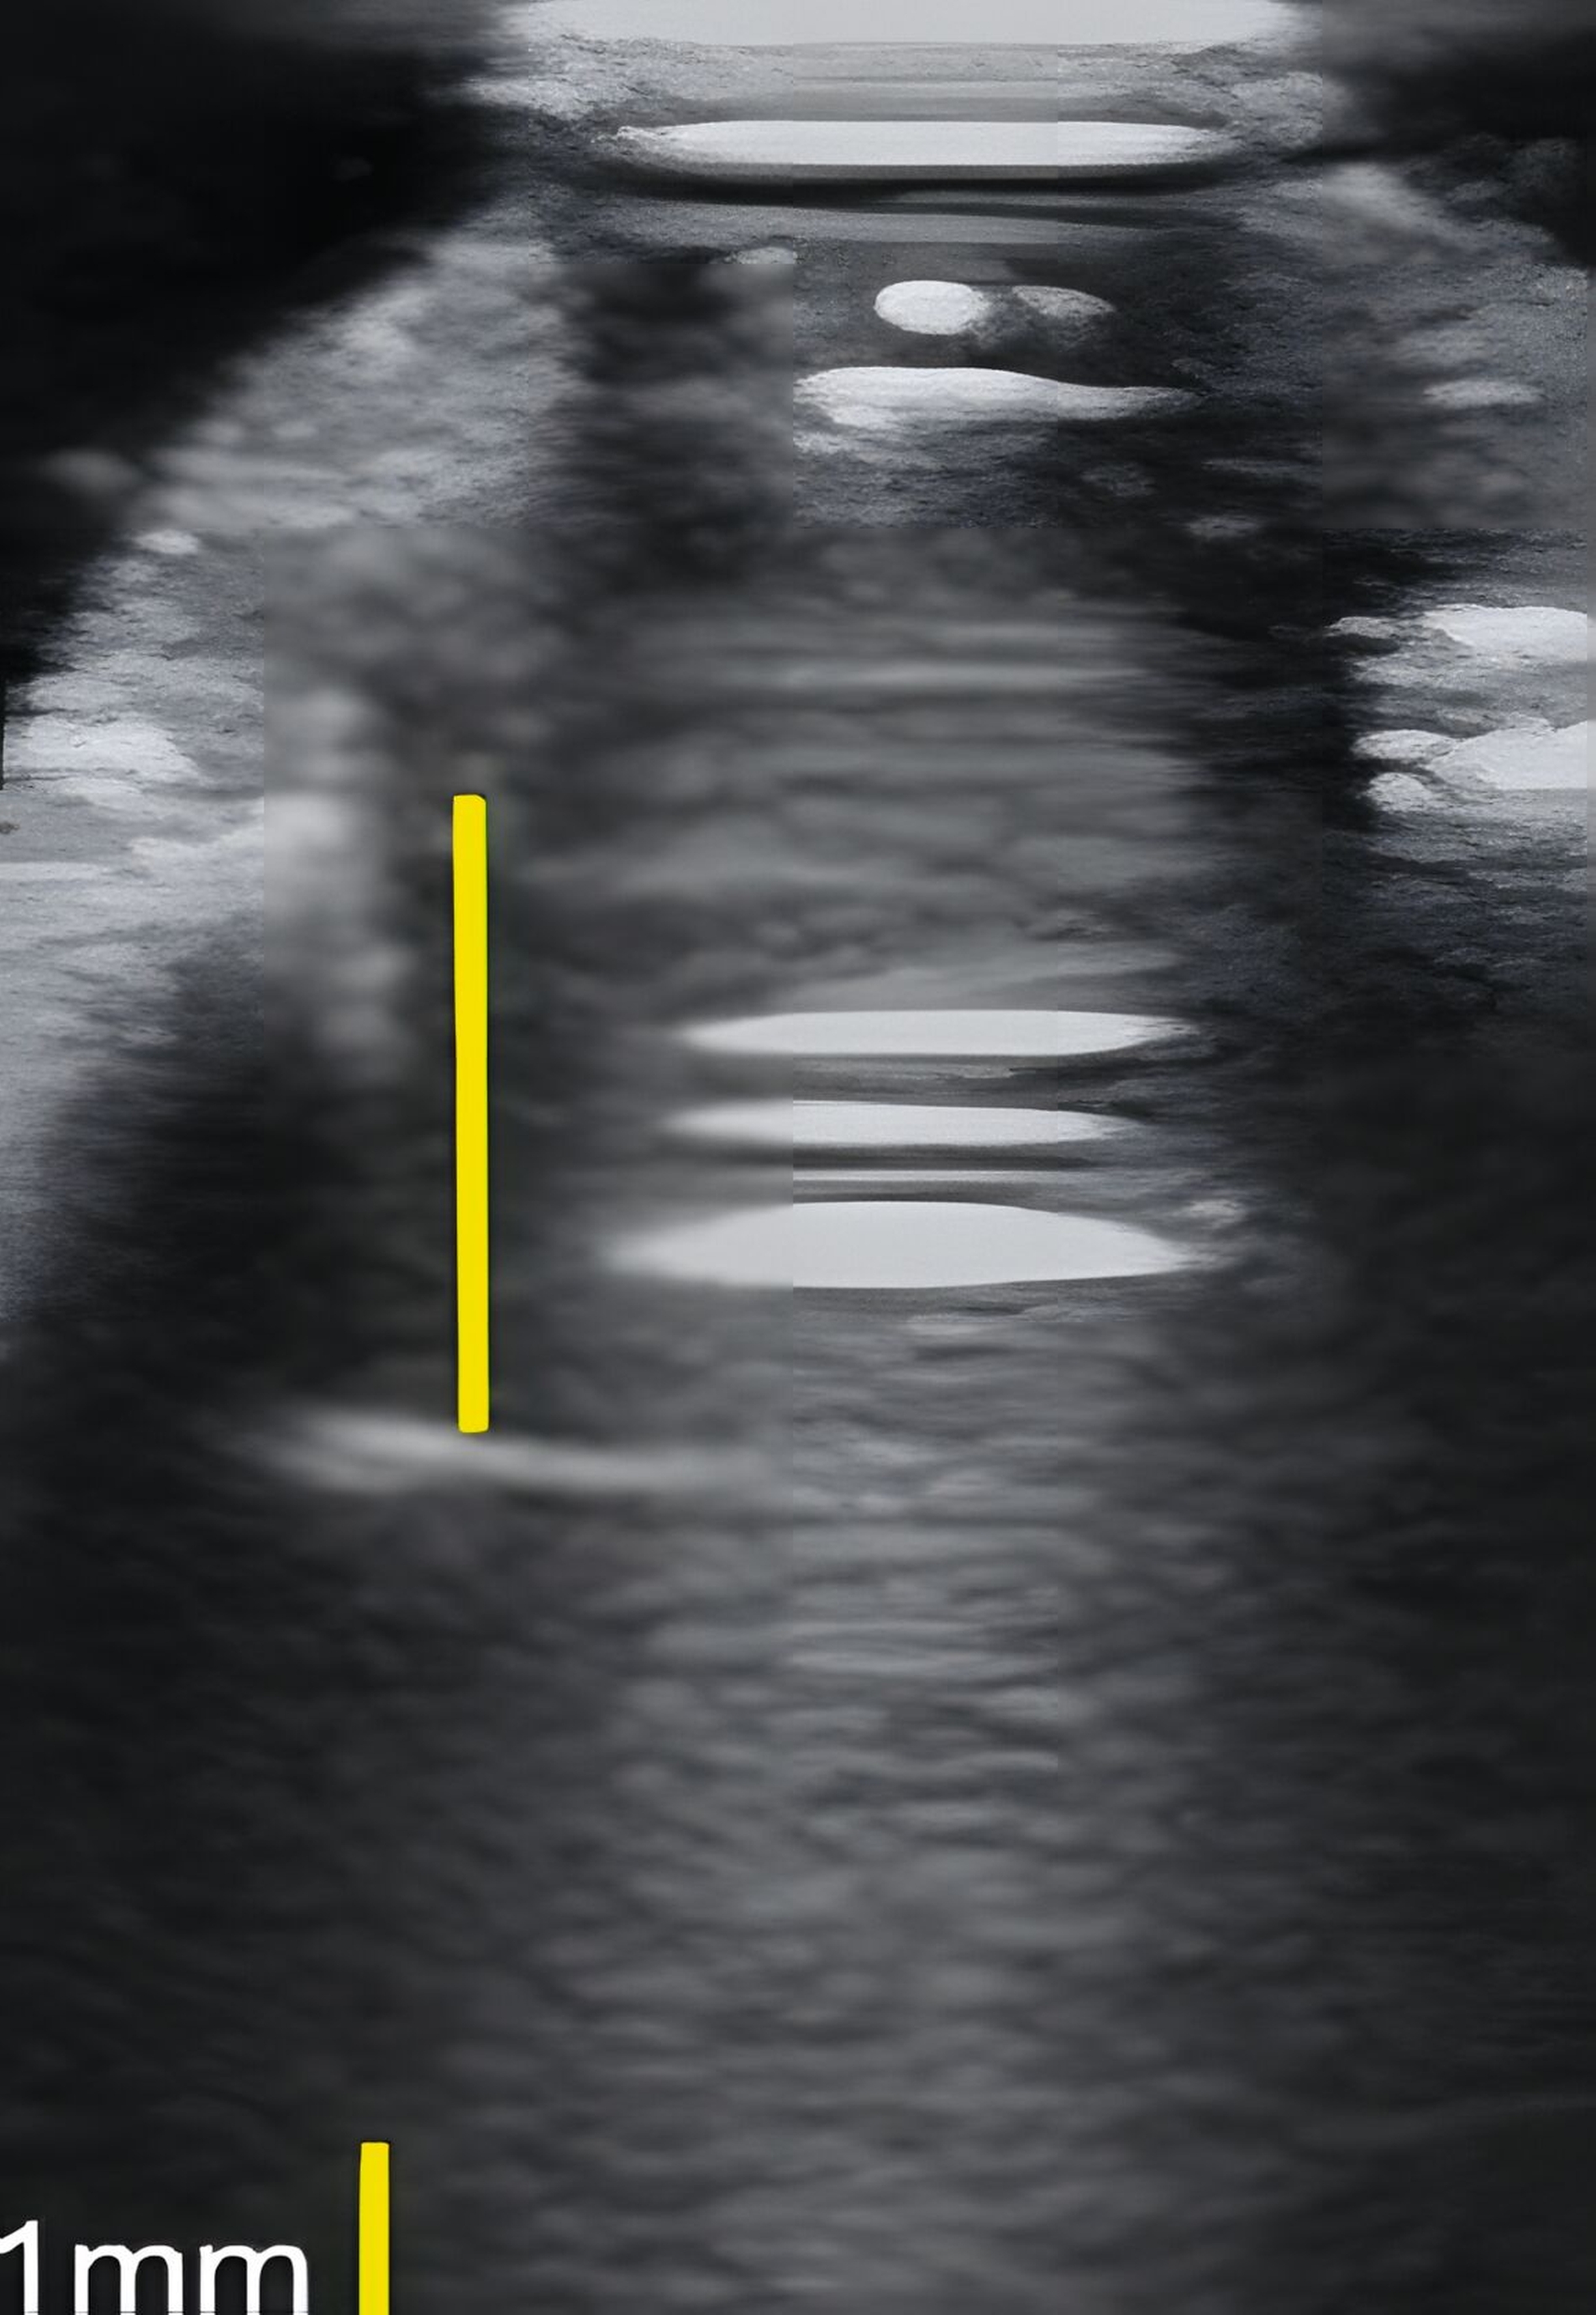

An Zähnen und Implantaten konnten das krestale Knochenniveau und die Weichgewebsdimension exakt anatomisch dargestellt werden (Abbildungen 3 und 4). An Implantaten erfolgte in einer humanen Kadaverstudie der Vergleich zwischen US- und direkten Messungen in Bezug auf die Höhe und die Dicke des Knochenniveaus und des Weichgewebes [Chan et al., 2018]. Die Korrelationen zwischen den US- und den direkten Messungen reichten von 0,92 bis 0,98 (p < 0,0001).

Dies konnte in einer ebenfalls eigenen humanen Kadaverstudie bestätigt werden [Bykhovsky et al., 2024]. Dabei wurden an Implantaten standardisiert Fenestrationen (n = 7), Dehiszenzen (n = 14) und dreiwandige Knochendefekte (n = 6) präpariert (Abbildungen 6 bis 8). Die Defekte wurden mit US- und DVT-Aufnahmen untersucht und die Messungen mit den direkten Messungen verglichen. Die US-Messungen zeigten eine starke Korrelation mit den direkten und den DVT-Messungen. Die sonografische Messgenauigkeit war bei Dehiszenzen am höchsten, gefolgt von Fenestrationen und dreiwandigen Knochendefekten.